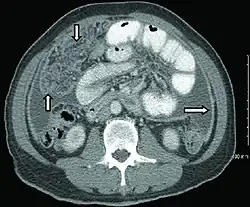

Abdominal infections include gastrointestinal tuberculosis (which is important to distinguish from Crohn's disease, since immunosuppressive therapy used for the latter can lead to dissemination), tuberculous peritonitis, and genitourinary tuberculosis.[4]

Urogenital tuberculosis represents the second most frequent form of extrapulmonary tuberculosis, accounting for 30-40% of cases. Primarily affecting males in their fourth and fifth decades, decades after initial infection and pulmonary manifestations, the disease reactivates from bacteria colonizing the kidneys, prostate, and/or epididymis, with subsequent descending infection through the renal collecting system. The insidious progression typically produces symptoms only at advanced stages, and is frequently misdiagnosed as a common UTI, leading to diagnostic delay and organ destruction. Key clinical presentations include storage symptoms (frequency, nocturia, urgency) in 50.5% of cases, hematuria (35.6%), lumbar or flank pain (34.4%), and scrotal abnormalities (48.9% of males). Diagnosis requires culture or PCR detection of Mycobacterium tuberculosis in urine, supplemented by imaging studies showing characteristic findings such as calyceal irregularities, renal infundibular stenosis, and multiple ureteral strictures. If untreated, the condition can progress from unilateral renal involvement to fibrotic bladder damage with contraction, and potentially bilateral kidney involvement through vesicoureteral reflux, culminating in end-stage renal failure.[11]